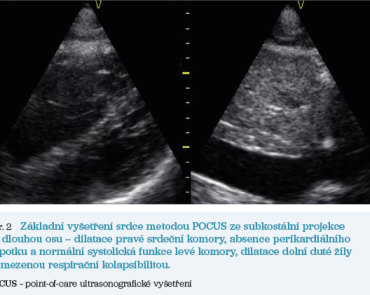

Návštěva lékaře byla realizována týž den ihned po skončení běžných ordinačních hodin. Při příchodu do ubytovny místnost silně páchne močí a stolicí, mlžný opar cigaretového kouře halí celý prostor, ze dveří vybíhají tři kočky. Při chůzi ode dveří k lůžku se pacientka zadýchává. Při vyprávění příběhu o transportu sanitou do nemocnice se nezadýchá. Pod pohrůžkou, že vyskočí za jízdy ze sanity, donutila řidiče zastavit. Jako důvod uvedla, že „V nemocnici lidi neléčí, jen jim dávají léky, aby si namastili kapsu. Od vás bych si nějaké léky asi i vzala, vás znám…“. Lékař provedl na místě klinické vyšetření, které bylo včetně nálezu na pravé dolní končetině podobné jako při vyšetření v ambulanci před třemi dny, pouze navíc zjistil zvýšenou tělesnou teplotu 37,5 °C, hraniční tepovou frekvenci 90/min, arteriální hypertenzi 170/100 mm Hg a hypoxii s SpO2 89 %. Orientační pletysmografické vyšetření prstce pravé dolní končetiny přenosným oxymetrem ukázalo viditelný rozpad křivky s neměřitelnou SpO2 a perfuzním indexem. Přenosným ultrazvukovým přístrojem bylo na místě zopakováno POCUS hlubokého žilního řečiště pravé dolní končetiny v rozsahu dvoumístné kompresivní ultrasonografie s trvajícím nálezem odpovídajícím trombóze ve v. poplitea a základní vyšetření srdce ze subkostální projekce na dlouhou osu prokázalo dilataci pravé srdeční komory, dilataci dolní duté žíly s omezenou respirační kolapsibilitou, absenci perikardiálního výpotku a normální systolickou funkci levé komory (obr. 2). Pracovní diagnóza erysipelu v oblasti bérce pravé dolní končetiny s komplikující popliteální hlubokou žilní trombózou byla doplněna o podezření na plicní embolii s obrazem akutního cor pulmonale se středním rizikem časného úmrtí a pacientka byla ihned odeslána k hospitalizaci prostřednictvím Zdravotnické záchranné služby.